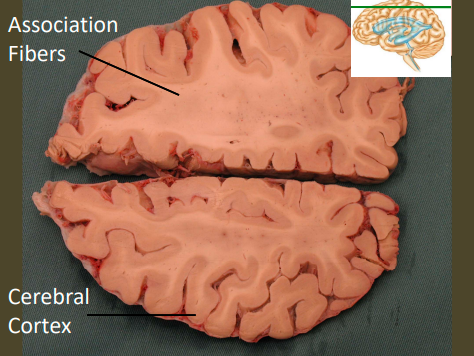

lable, note important features

label, note important features